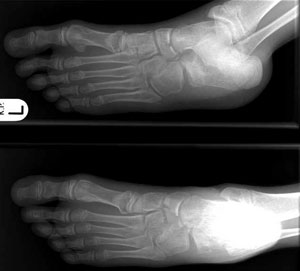

Metatarsals

Fracture 1st metacarpel / cuniform /navicular / distal calcaneum

-

Undisplaced - lower leg plaster slab, fracture clinic with Xray in 7 days.

Displaced - seek advice; may need admission under Orthopaedics.